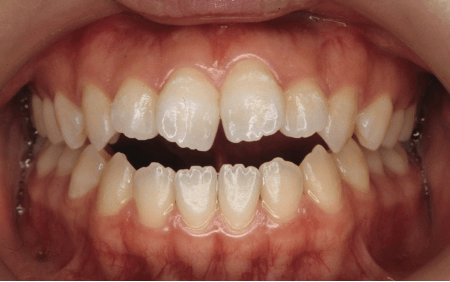

OPENBITE

「前歯で食べ物を噛み切れない」「話すときに息が漏れる気がする」そんなお悩みをお持ちではないですか?

開咬とは、奥歯を噛み合わせたときに上下の前歯の間に隙間ができてしまう状態のことです。

正常な噛み合わせでは上と下の歯がしっかり当たりますが、開咬では前歯が当たらないため、食べ物を前歯でかみ切ることができません。

放置すると噛み合わせの悪化が進みやすく、食事のしにくさや発音のしづらさ(特にタ行・サ行)につながることがあります。

一度、開咬となると舌を歯と歯の間に挟まないと食べ物を飲み込むことができず、悪化をし続けてしまいます。